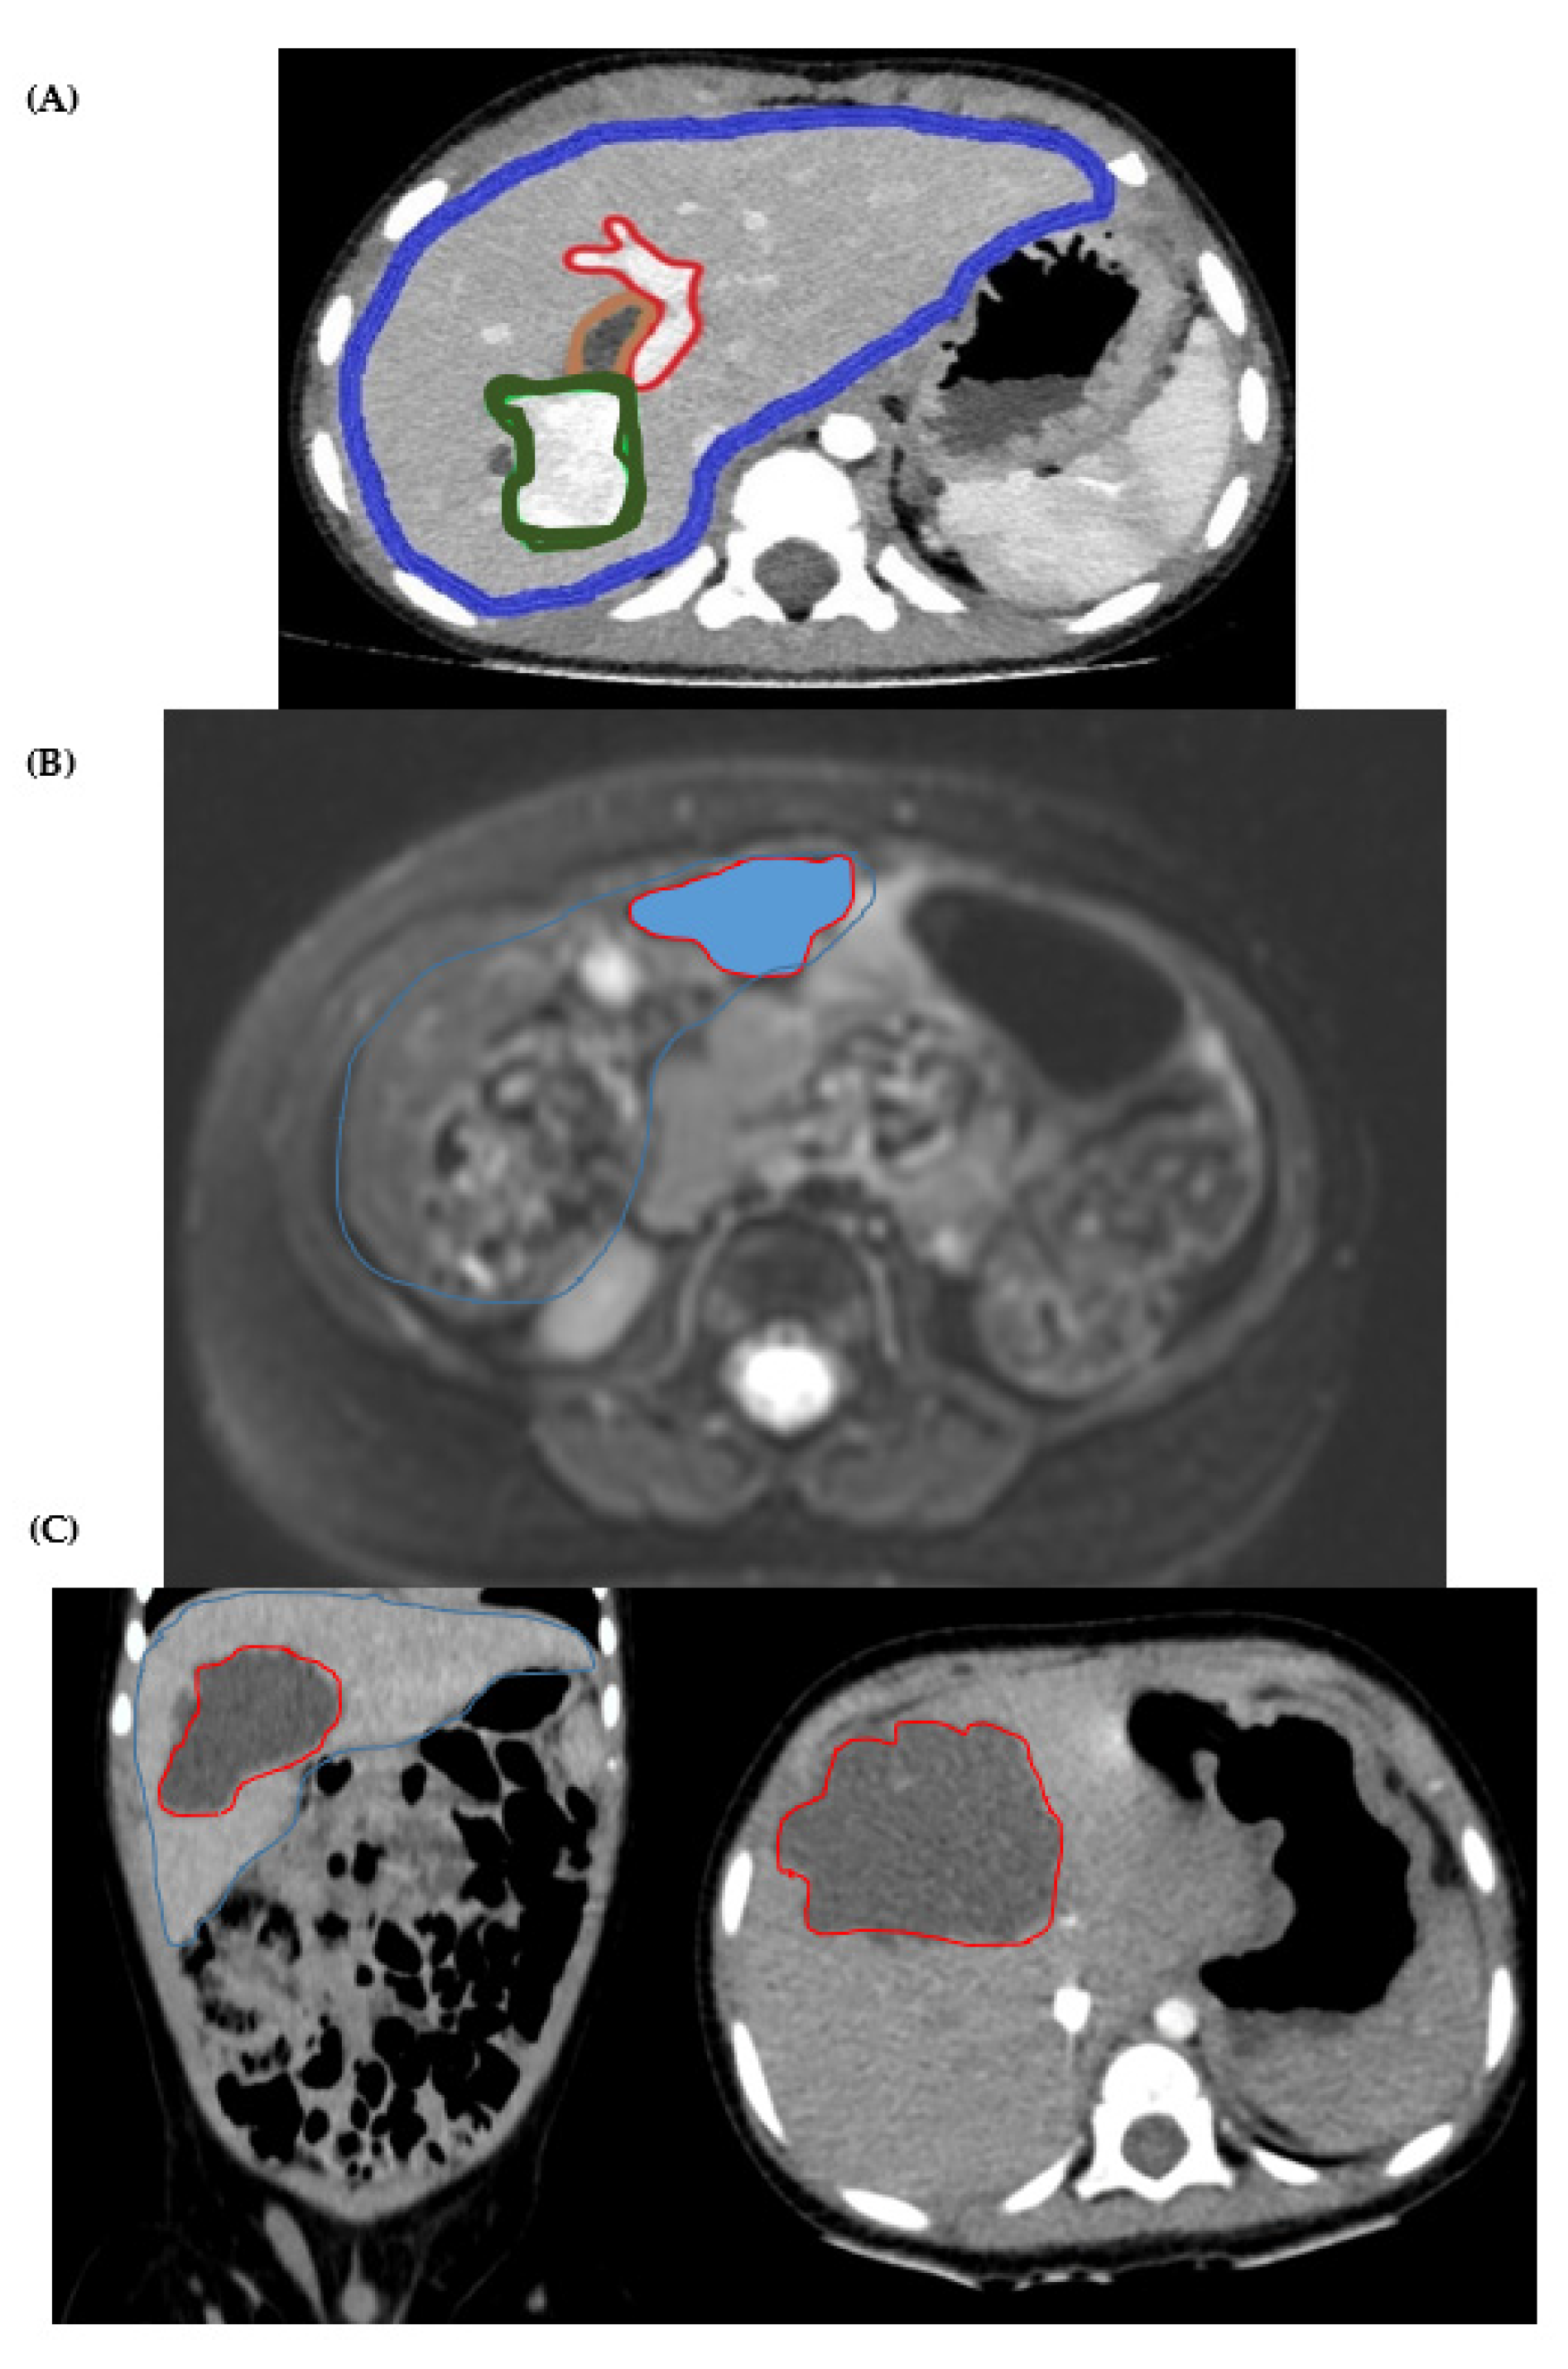

4.1. Cases Presentation

4.3. Image Acquisition

4.4. Image Segmentation and Surface Reconstruction